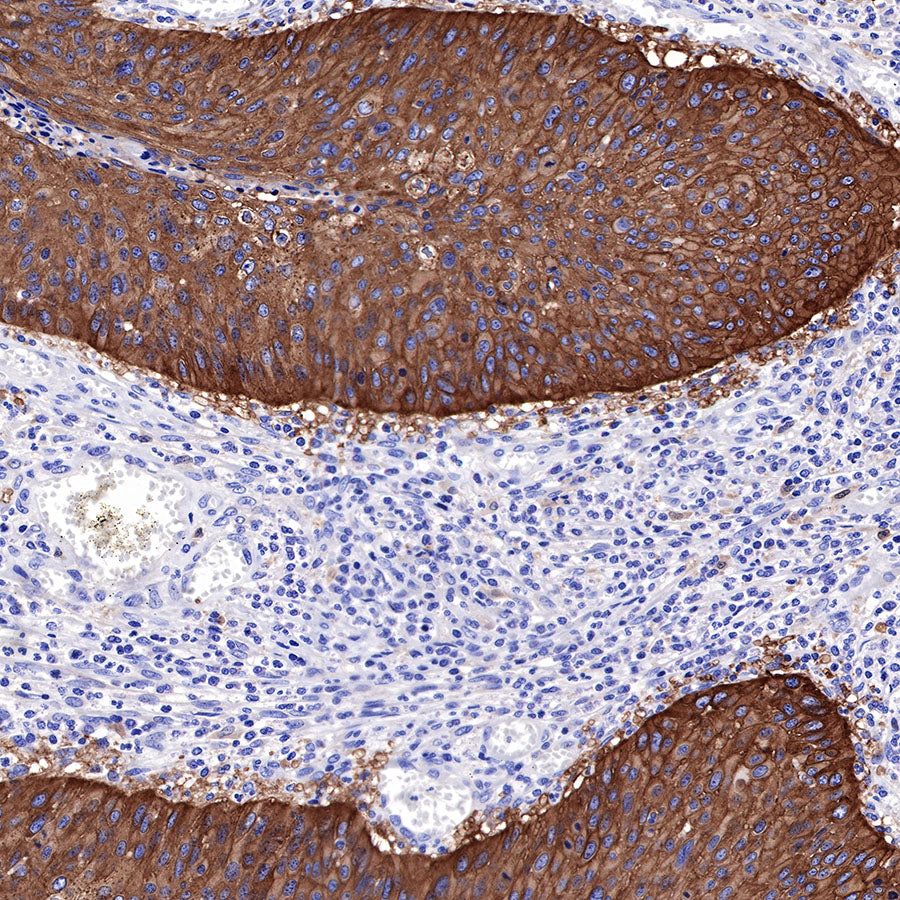

IHC shows positive staining in paraffin-embedded human esophagus. Anti-EGFR antibody was used at 1/2000 dilution, followed by a HRP Polymer for Mouse & Rabbit IgG (ready to use). Counterstained with hematoxylin. Heat mediated antigen retrieval with Tris/EDTA buffer pH9.0 was performed before commencing with IHC staining protocol.

IHC shows positive staining in paraffin-embedded human cervical squamous cell carcinoma. Anti-EGFR antibody was used at 1/2000 dilution, followed by a HRP Polymer for Mouse & Rabbit IgG (ready to use). Counterstained with hematoxylin. Heat mediated antigen retrieval with Tris/EDTA buffer pH9.0 was performed before commencing with IHC staining protocol.